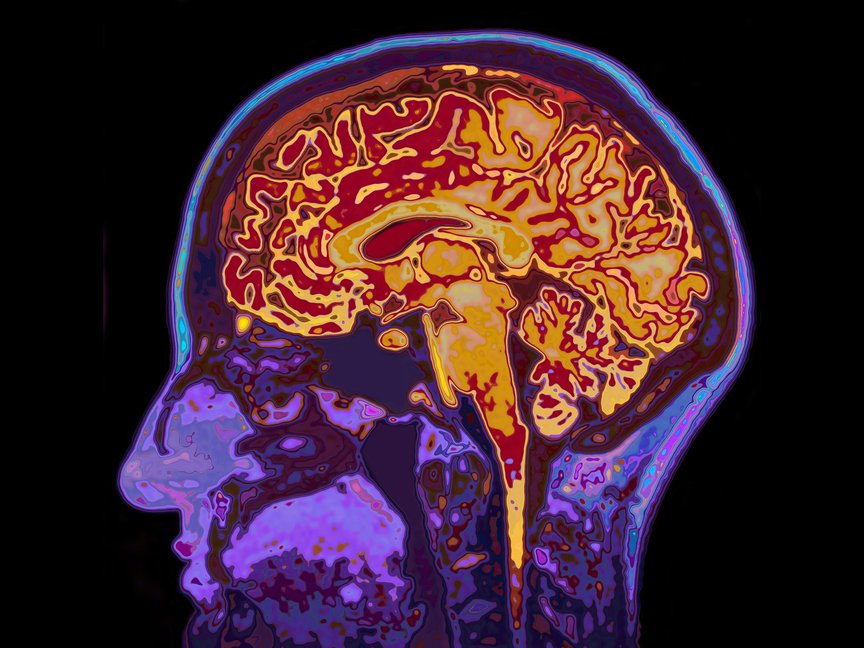

Brains don’t talk much, as a rule. But they’re not quiet, either—fizzing with message-carrying molecules among an uncountably complicated thicket of neurons. Still, despite the seeming ubiquity of functional magnetic resonance imagery in stories about “the part of the brain that controls X,” scientists don’t really know what’s going on in there. Functional MRI images actually blur spatially over relatively huge chunks of think-meat, and over several seconds of time. Very low resolution. Electroencephalograms take a faster snapshot, but of the entire brain at once. So neural interfaces like the ones Chang uses—deployed in the past to allow physically paralyzed people to control computers—offer an opportunity for more detailed “electrocorticography,” reading the activity of the brain more directly.